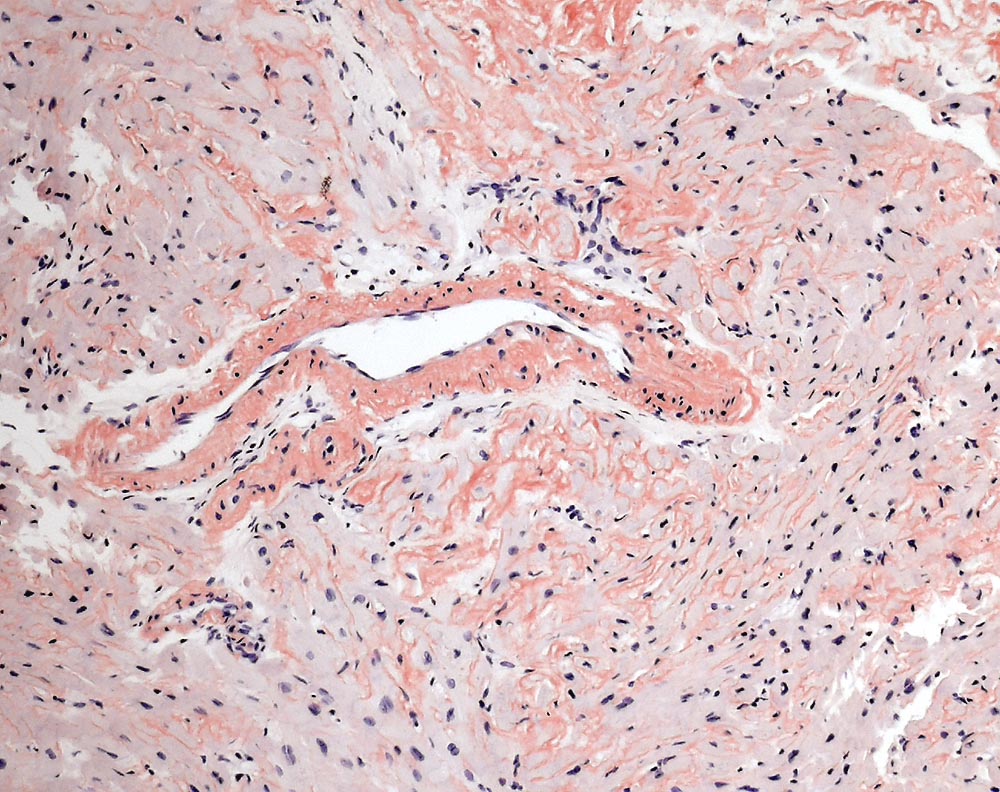

Kardiale AL-Amyloidose

Interstitielle und vaskuläre kongorote Amyloidablagerungen.

Interstitielle Knochenmarksinfiltration durch ein lambdaklonale Plasmazellneoplasie, Infiltrationsvolumen 15-20% der kernhaltigen Knochenmarkszellen. AL-Amyloidose der Knochenmarksgefässe.

Zunehmende Dyspnoe über die vergangenen 2 Jahre. Multiples Myelom mit freien Leichtketten vom Typ Lambda. TTE: Ausgeprägt konzentrisch hypertropher linker Ventrikel mit normaler systolischer Globalfunktion ohne regionale Motilitätsstörungen (EF 60%). Diastolische Dysfunktion Grad 3 bis 4 (restriktive Füllungsmuster).

Histologie

Vergrösserung